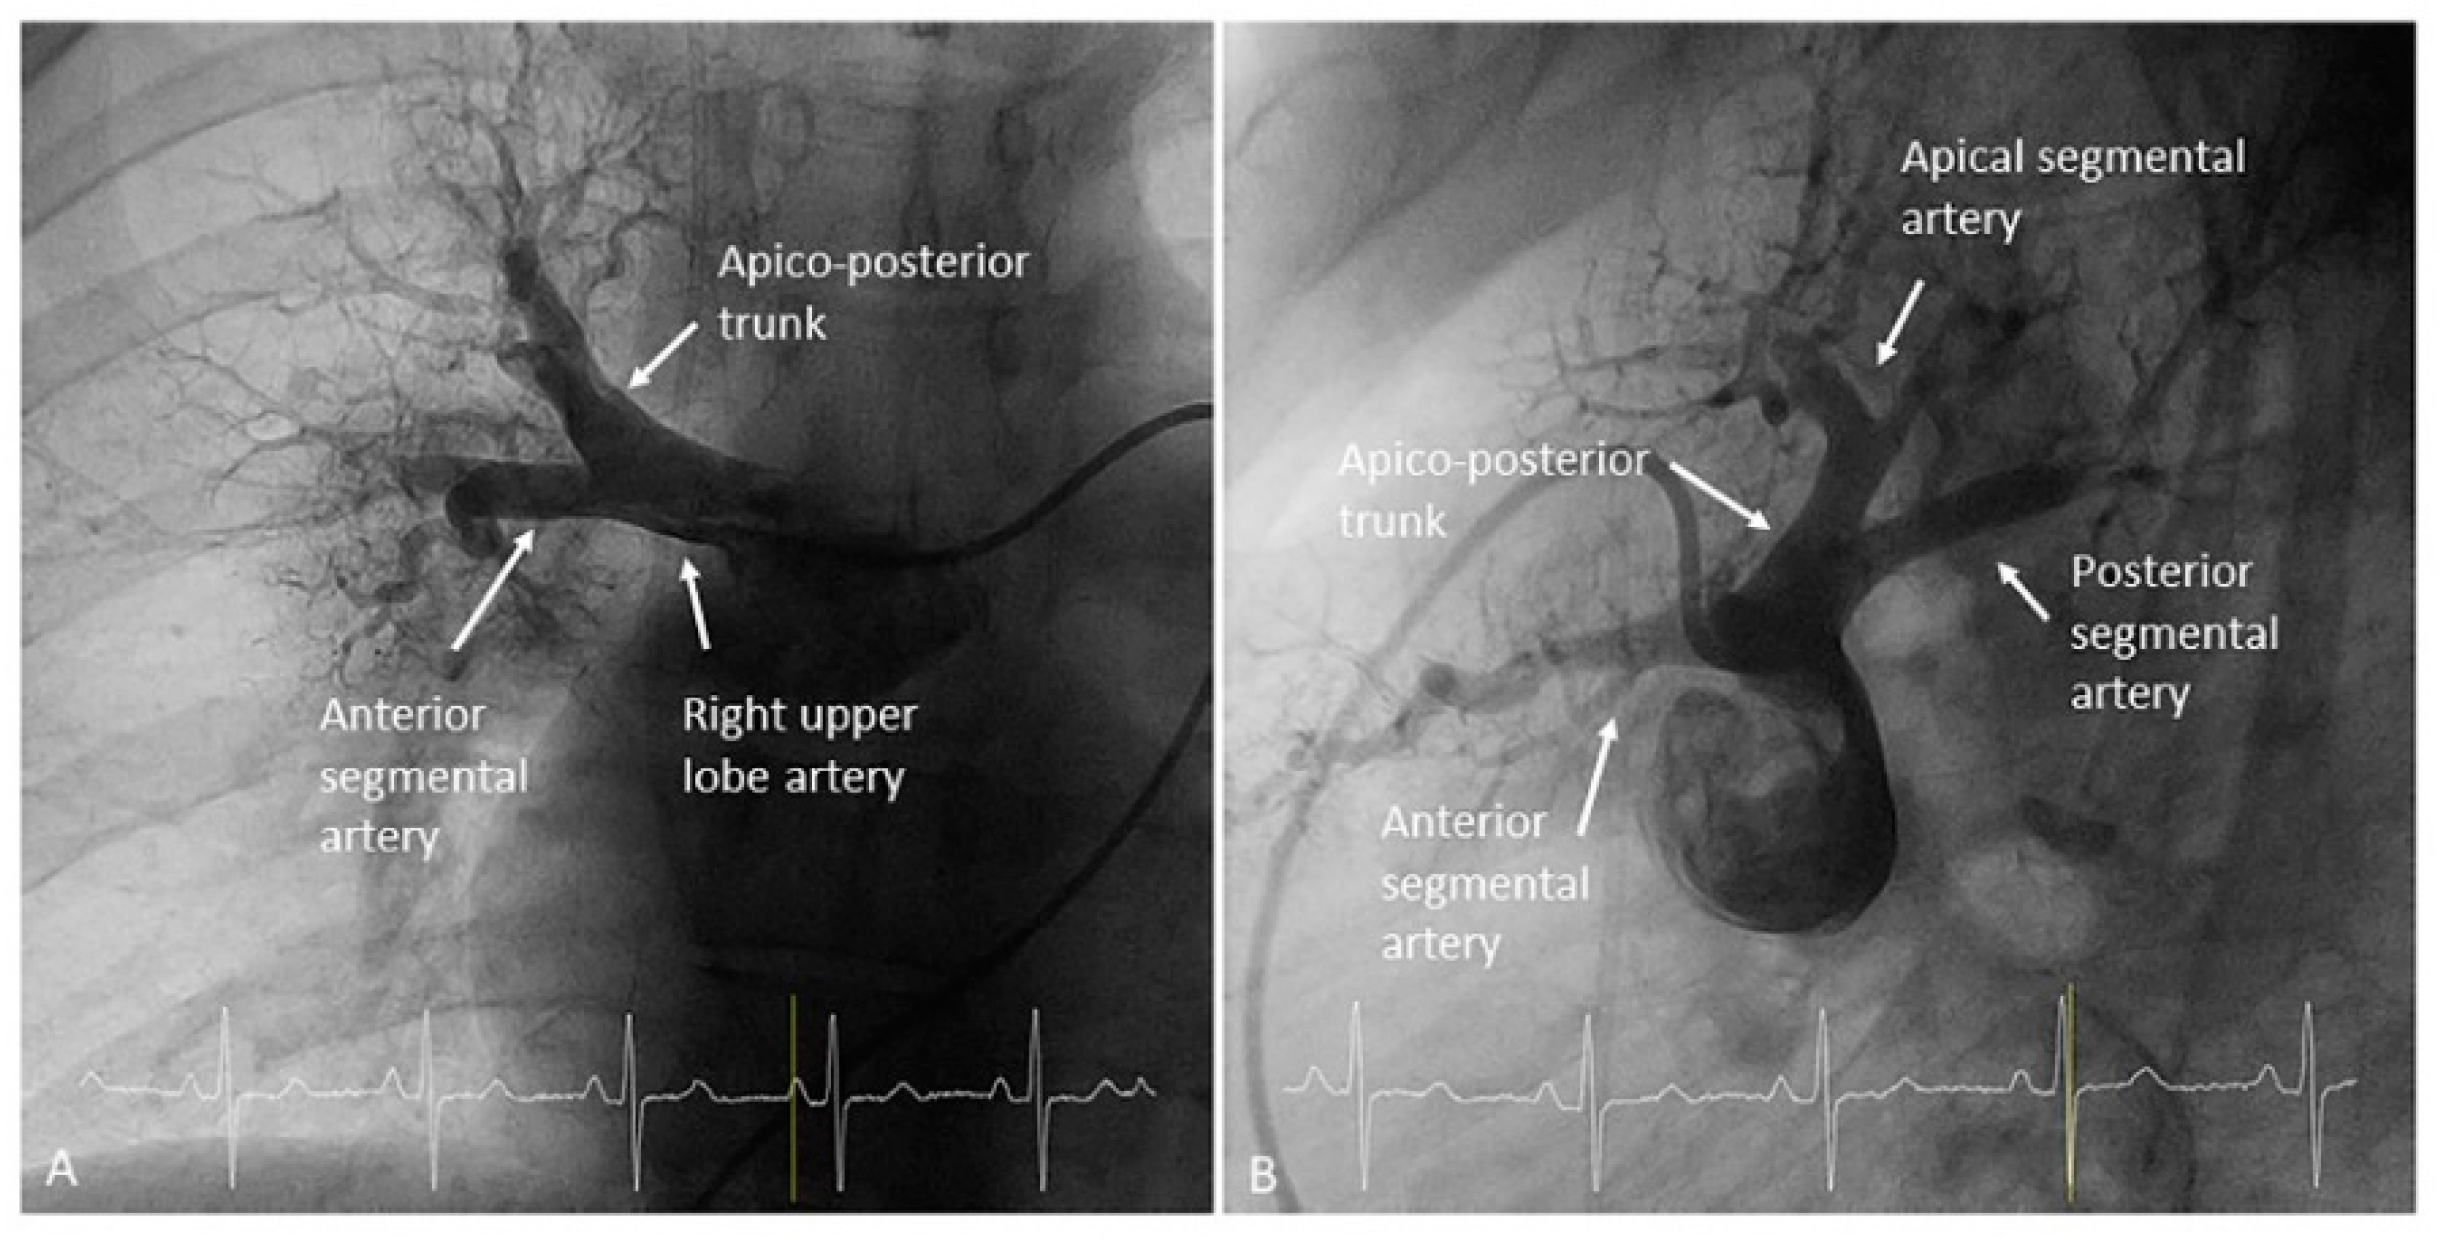

- Left upper lobe. The apico-posterior trunk (A1/2) is easily cannulated in the AP view. We should rotate the MP-A2 catheter counterclockwise in the proximal segment of the LPA to make the tip face upwards (Figure 23). The apical and posterior segmental arteries (A1 and A2) are well visualized by filming in the AP and lateral views. The anterior segmental artery (A3) is engaged more easily with the Judkins left catheter (JL) 3.5 or 4. Position the JL below the aortic arc in the AP view with the distal tip facing the left lateral chest wall. Rotate the catheter counterclockwise and withdraw it slightly. The distal tip of the catheter will climb 2–3 cm, engaging the anterior segmental branch (A3) (Figure 24). Film this branch in the cranial RAO and lateral views.

- Right upper lobe. The right upper lobar artery arises about 10 cm from the bifurcation. It is cannulated in the AP view with the tip of the MP-A2 facing upwards. The apico-posterior segmental artery (A1/2) is canalized just by advancing the MP distally once in the right upper lobe artery. The AP and lateral views display the apical (A1) and posterior branches (A2) (Figure 28). The anterior segmental artery (A3) is canalized in the lateral view, rotating the MP counterclockwise from its position in the apico-posterior artery (A1/2). With this maneuver, the tip of the catheter moves downwards, facing the sternum and engaging the anterior segmental artery (A3) (Figure 29). This branch should be filmed in lateral and cranial AP/cranial LAO view.